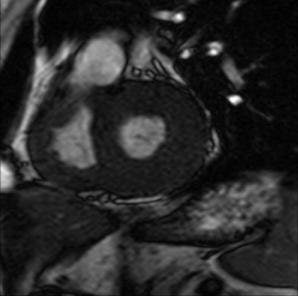

![]() |

| MRI of a patient with left and right ventricular hypertrophy due to Fabry's disease. Image courtesy of Dr. Wolfram Machann. |

For their study, 59 patients with genetically proven Fabry's disease underwent 1.5-tesla MR scans prior to enzyme therapy. Twenty patients were available for follow-up and two healthy controls also underwent MR for comparison.

Their MRI protocol included steady-state-free-precision sequences to measure RV function and mass, as well as cine MRI to determine volume, Machann said. Thirty-nine patients were excluded from the study because of a change in MR protocol from a gradient-echo sequence to a steady-state-free-precession sequence, Machann explained.

For image analysis, the group determined the myocardial mass of the right ventricle, the end diastolic and end systolic volume (from which the stroke volume and ejection fraction were determined). All these parameters were computed in absolute values and normalized to body surface using Argus Software (Varian Medical Systems, Palo Alto, CA).

According to the results, the RV ejection fraction at baseline was 55 ± 6%, which was significantly lower than the control group. During one year of therapy, RV ejection fraction improved to 59 ± 6%. There was also a tendency toward a higher value for the RV mass and a significant difference in systolic and anasytolic volume. His group concluded that RV function can be used as a therapy control parameter in Fabry's disease.